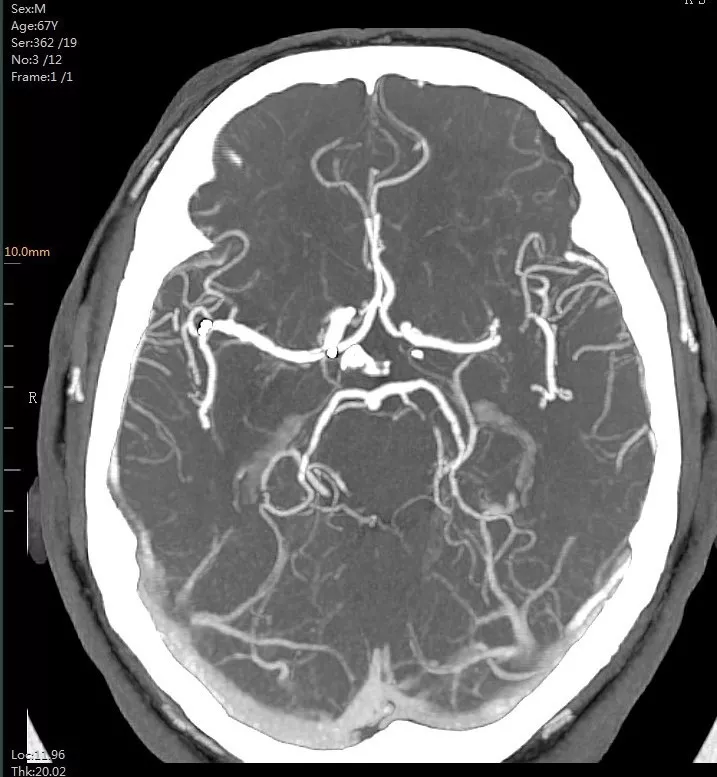

9:40分左右,患者逐渐开始出现烦躁、嗜睡,查体:言语不清,左侧肢体肌力0-1级,急查头颅MRI+MRA+颈部MRA阅片见,右侧基底节区急性脑梗死,右侧大脑中动脉闭塞。

头颅MRI+MRA(08-03日 11:50左右)

头颅MRI+MRA(2018-01-30日)

患者症状逐渐加重,头颅MRA示右侧大脑中动脉闭塞,是本次病灶责任血管,目前患者在取栓时间窗内,有行桥接动脉机械取栓指征。与患者家属沟通后全麻下行右侧大脑中动脉取栓术。手术风险及相关注意事项向患者家属告知。

术后头颈部CTA(08-07日 17:23分)